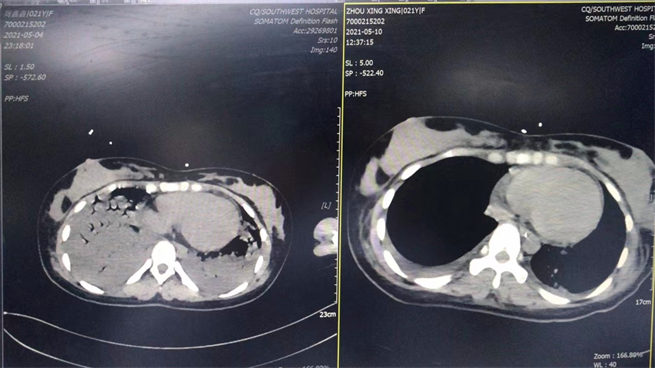

5月4日是剛轉進科時和5月10日是撤ecom后做的CT對比圖。西南醫(yī)院供圖!